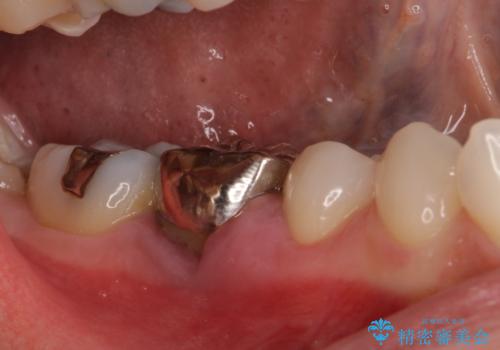

機能性と清掃性、更には審美性も考慮し、土台となるアバットメントにはジルコニアカスタムアバットメントを採用しました。

ジルコニアカスタムアバットメントは、歯肉ラインに金属が見えにくいというだけでなく、クラウンを装着する土台の形が天然歯と近い形態となるため、清掃性が高く歯肉が腫れにくいというメリットがあります。